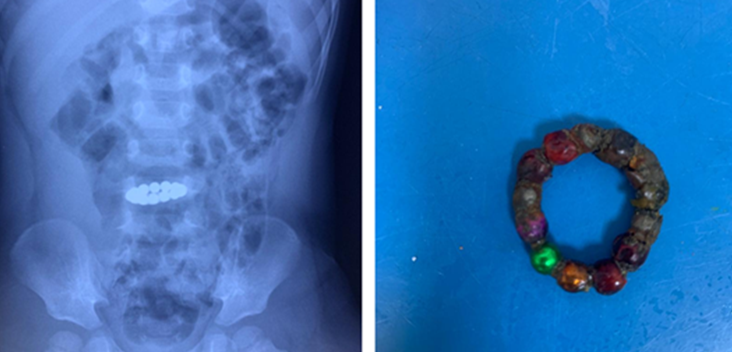

Tại đây, trẻ nôn ói, quấy khóc, đau bụng. Khi chụp X-quang bụng, bác sĩ nhận thấy dị vật còn ở ruột non nên tiến hành nội soi đường tiêu hóa cấp cứu và nội soi ổ bụng. Dị vật gây gập góc đoạn hỗng tràng thành một vòng viêm dính, thủng bít.

Các bác sĩ ngoại khoa quyết định cắt bỏ đoạn ruột viêm dính gập góc (khoảng 7cm) và nối ruột. Đồng thời, lấy ra 14 viên bi màu sắc khác nhau, một số viên rỉ sét gây tổn thương ruột nghiêm trọng. Sau một tuần phẫu thuật, trẻ hết đau bụng, hết ói, tỉnh táo và phải theo dõi tổn thương niêm mạc ruột, chức năng đường tiêu hóa.